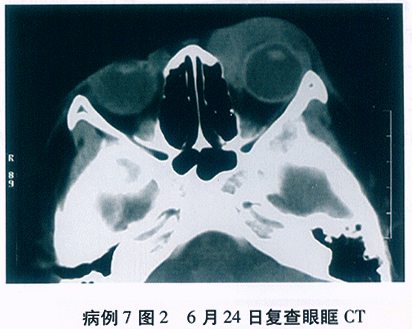

2日后复查B超(见图37-6)结论:右眼玻璃体前中段中-大量点状回声, 后极下方球壁前带状强回声,距离球壁1~3, 后极球壁前轻度隆起低-中等回声。后极偏下球外壁短条状强回声,声影, 左眼前中段少-中量点状回声,后极球壁前带状回声, 双眼玻璃体混浊伴后脱离可能,右眼网脱、后极脉络膜水肿增厚可能, 右眼球壁钙化?左眼后极网膜水肿低脱可能。

高频B超检查(见图37-7)结果: 右眼除上方外球壁前波浪样双线状回声,距离球壁1~3mm